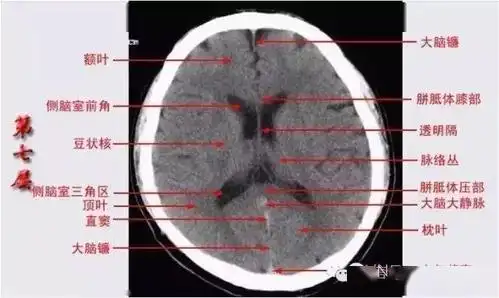

颅脑ct的正常解剖